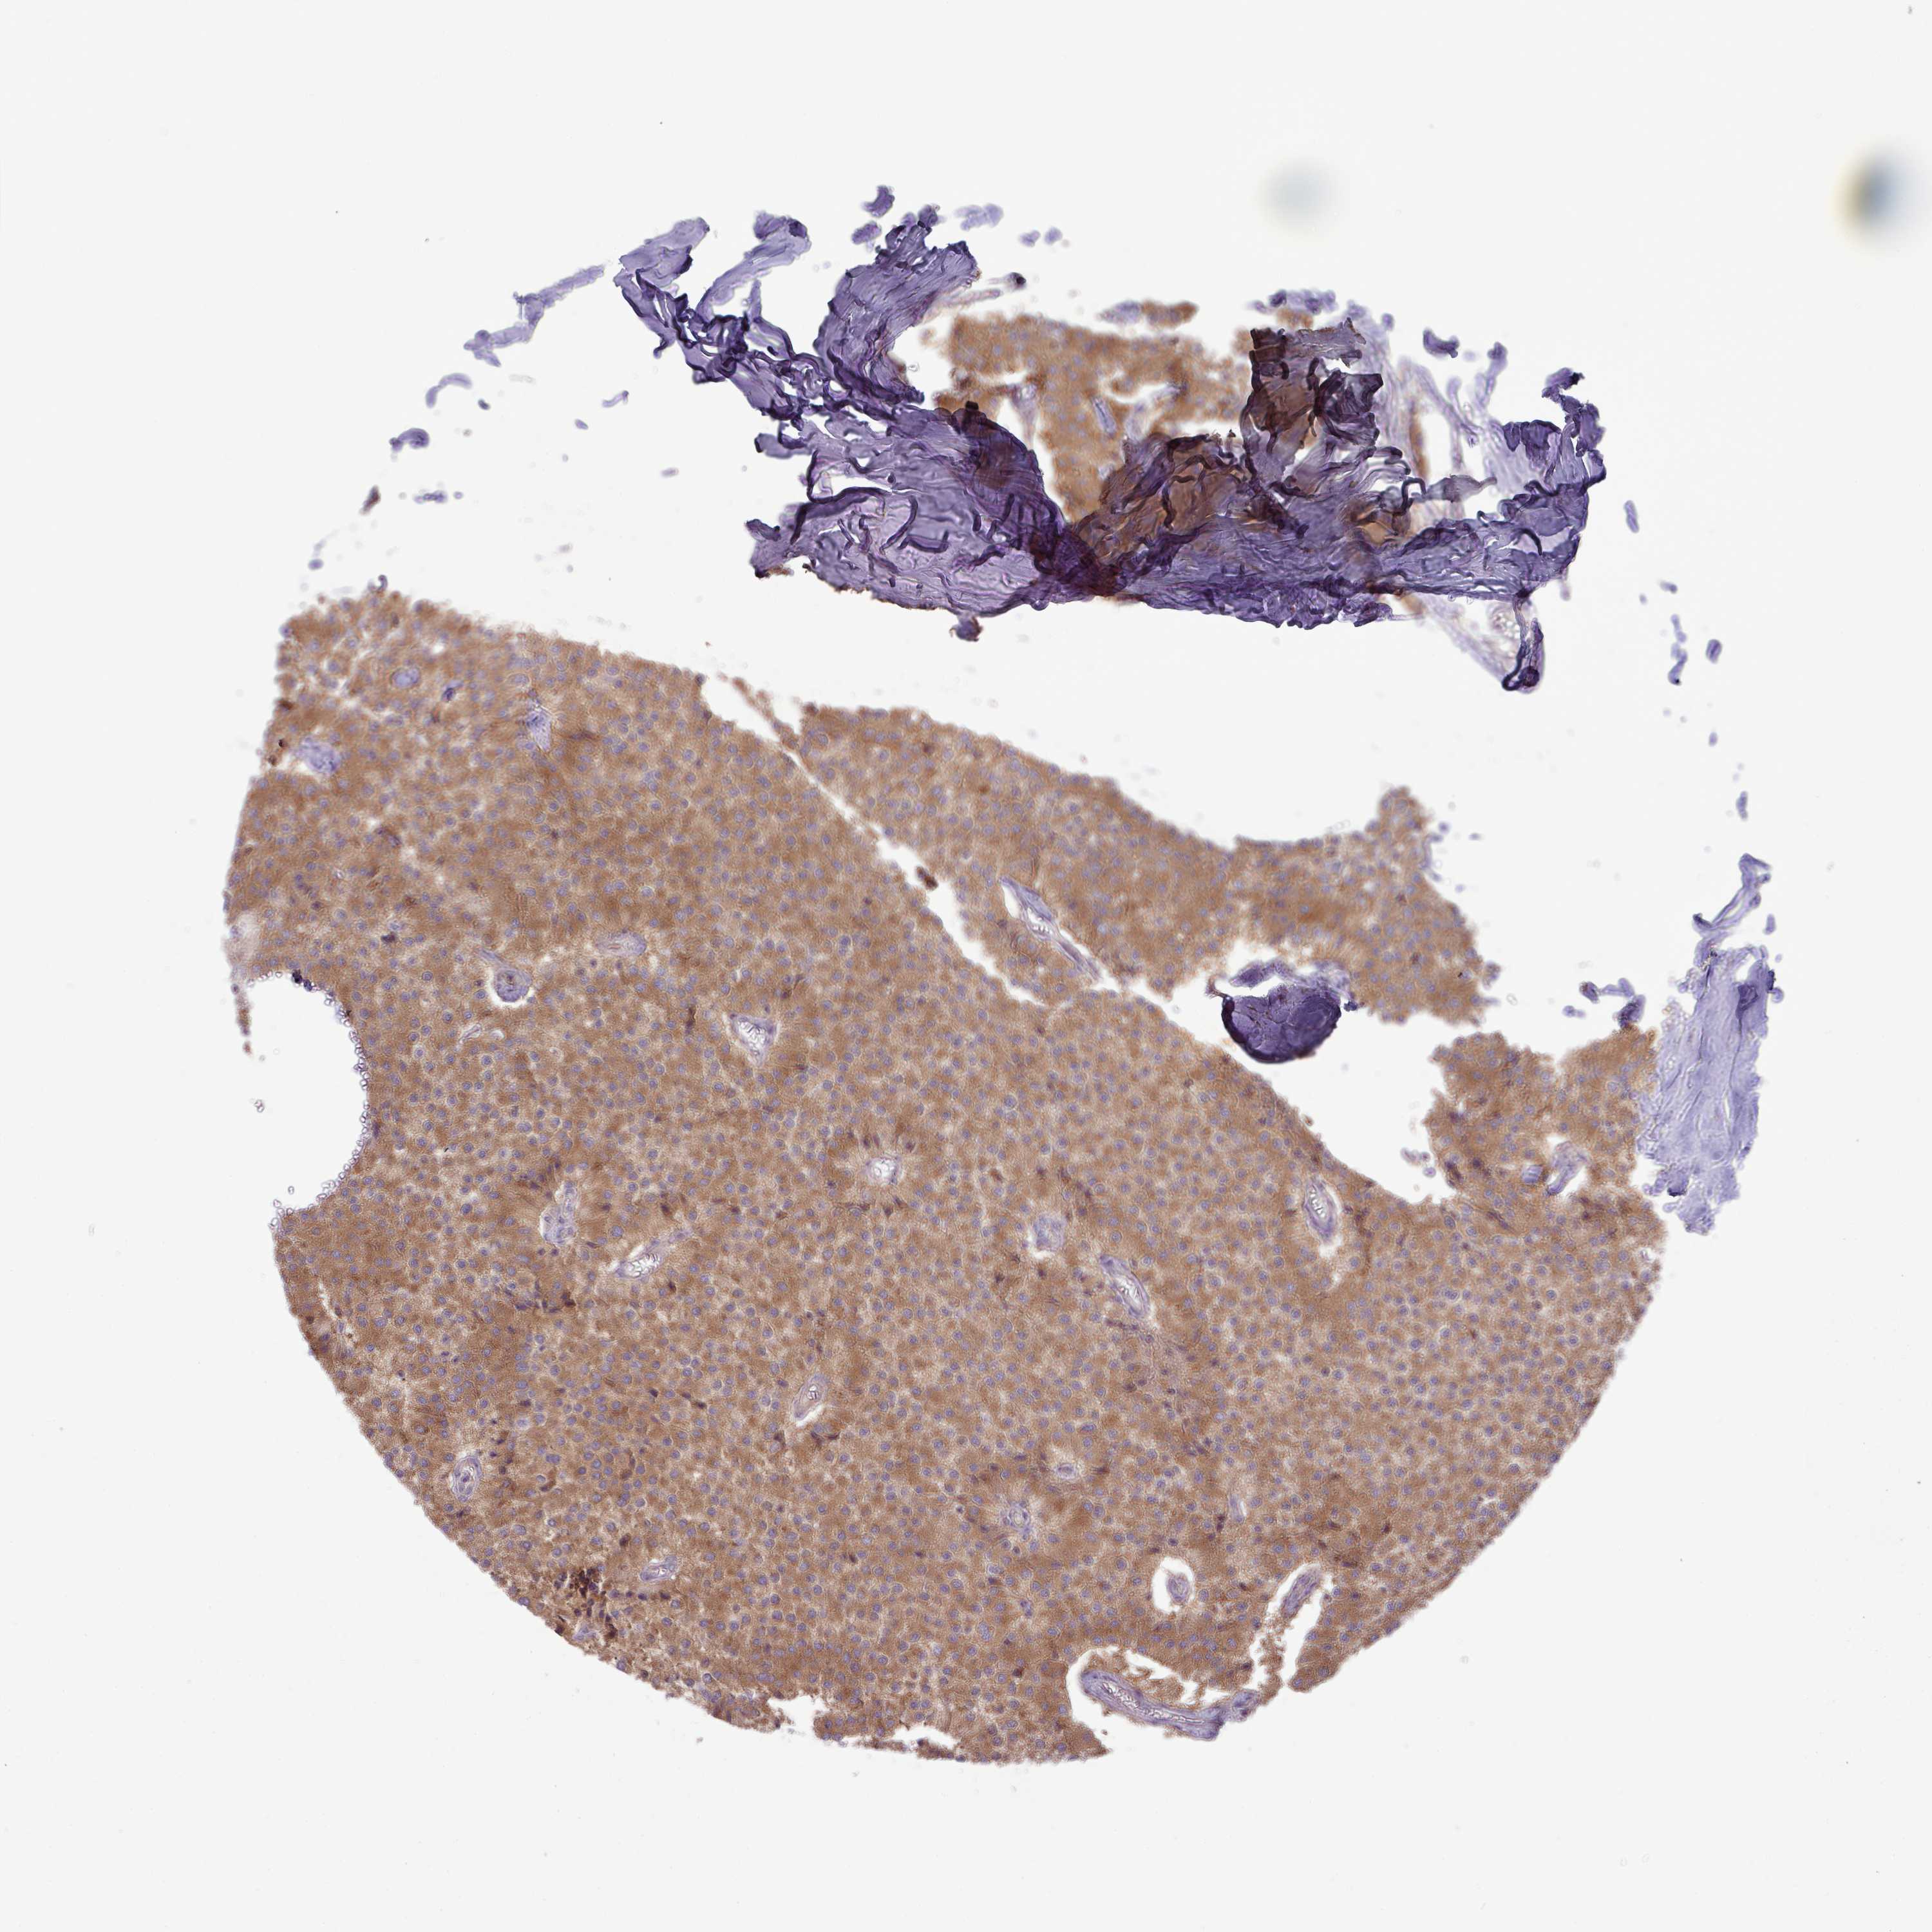

CARCINOID - Protein expressioni

A mouse-over function shows sample information and annotation data. Click on an image to view it in a full screen mode. Samples can be filtered based on level of antibody staining by selecting one or several of the following categories: high, medium, low and not detected. The assay and annotation is described here.

Each image is clickable and will lead to virtual microscopy that enables deeper exploration of all samples and also displays staining intensity scores, fraction scores and subcellular localization as well as patient and tissue information for each sample.

Antibody HPA051077

Staining

Low

Intensity

Weak

Quantity

<25%

Location

Cytoplasmic/membranous

Carcinoid, malignant, NOS

Carcinoma, NOS